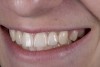

(2.) After orthodontic alignment of teeth and bleaching. Note alveolar deficiency in right lateral incisor site and diminutive left lateral incisor.

Figure 2

A 14-year-old patient presented to the office with his mother (Figure 1). His chief complaint involved the large spaces between the teeth created by his missing right maxillary lateral incisor and his small left maxillary lateral incisor. He desired to replace the missing tooth with an implant and create a beautiful smile. Upon examination, he was found to have a class I canine and molar relationship, but because he had a tooth size/arch size discrepancy and space distal to the right central incisor, the remaining incisors had drifted to the right. The left maxillary lateral incisor was peg-shaped and in a cross bite position. Studies have shown a clear association between congenitally missing teeth and reduced tooth size.59-62 Because he was only 14-years-old at the time and could not have implants placed until the cessation of growth (somewhere in the vicinity of 22 years old), he was sent to the orthodontist for alignment of the teeth.16,17 After 2 years of orthodontics, the appliances were removed, and his tooth coloration was improved using carbamide peroxide bleaching (Figure 2). Because some form of provisional needed to be placed until he was finished growing, a double-wing metal resin-bonded bridge was chosen. As discussed earlier, this is the ideal transitional prosthesis for patients that have congenitally missing maxillary lateral incisors. The benefits of this type of prosthesis include its ability to be removed and rebonded during the surgical phase of treatment and its ability to retain the roots in their proper position after orthodontic treatment.16 The final plan for the patient was to increase the width of the central and the maxillary left lateral incisor, utilizing porcelain laminate veneers to achieve the appropriate width/length ratio of 80%. A wax-up was created to idealize tooth size, a putty matrix was made from the wax-up to facilitate bonding of the incisors, and a non-precious, double-wing metal resin-bonded bridge was fabricated for lateral incisor replacement. Once the teeth were bonded to ideal size, the “Maryland Bridge” was fabricated from a polyvinyl arch impression with the newly bonded teeth (Figure 3). The metal frame was cast from a non-precious alloy to allow for fabrication of a very thin frame and to create a better surface for bonding. After sandblasting the internal aspect of the frame with CoJet™ silica (3M ESPE), accomplishing salinization, and executing cementation with a dual-cure resin cement, a fairly good adhesion to the frame was anticipated.29 The enamel surface was etched with phosphoric acid for 30 seconds, the primer (Single Bond Plus, 3M ESPE) was applied to both the internal surface of the sandblasted framework and the etched enamel, and the bridge was cemented with RelyX™ ARC (3M Espe) dual-cured resin cement (Figure 4 and Figure 5).